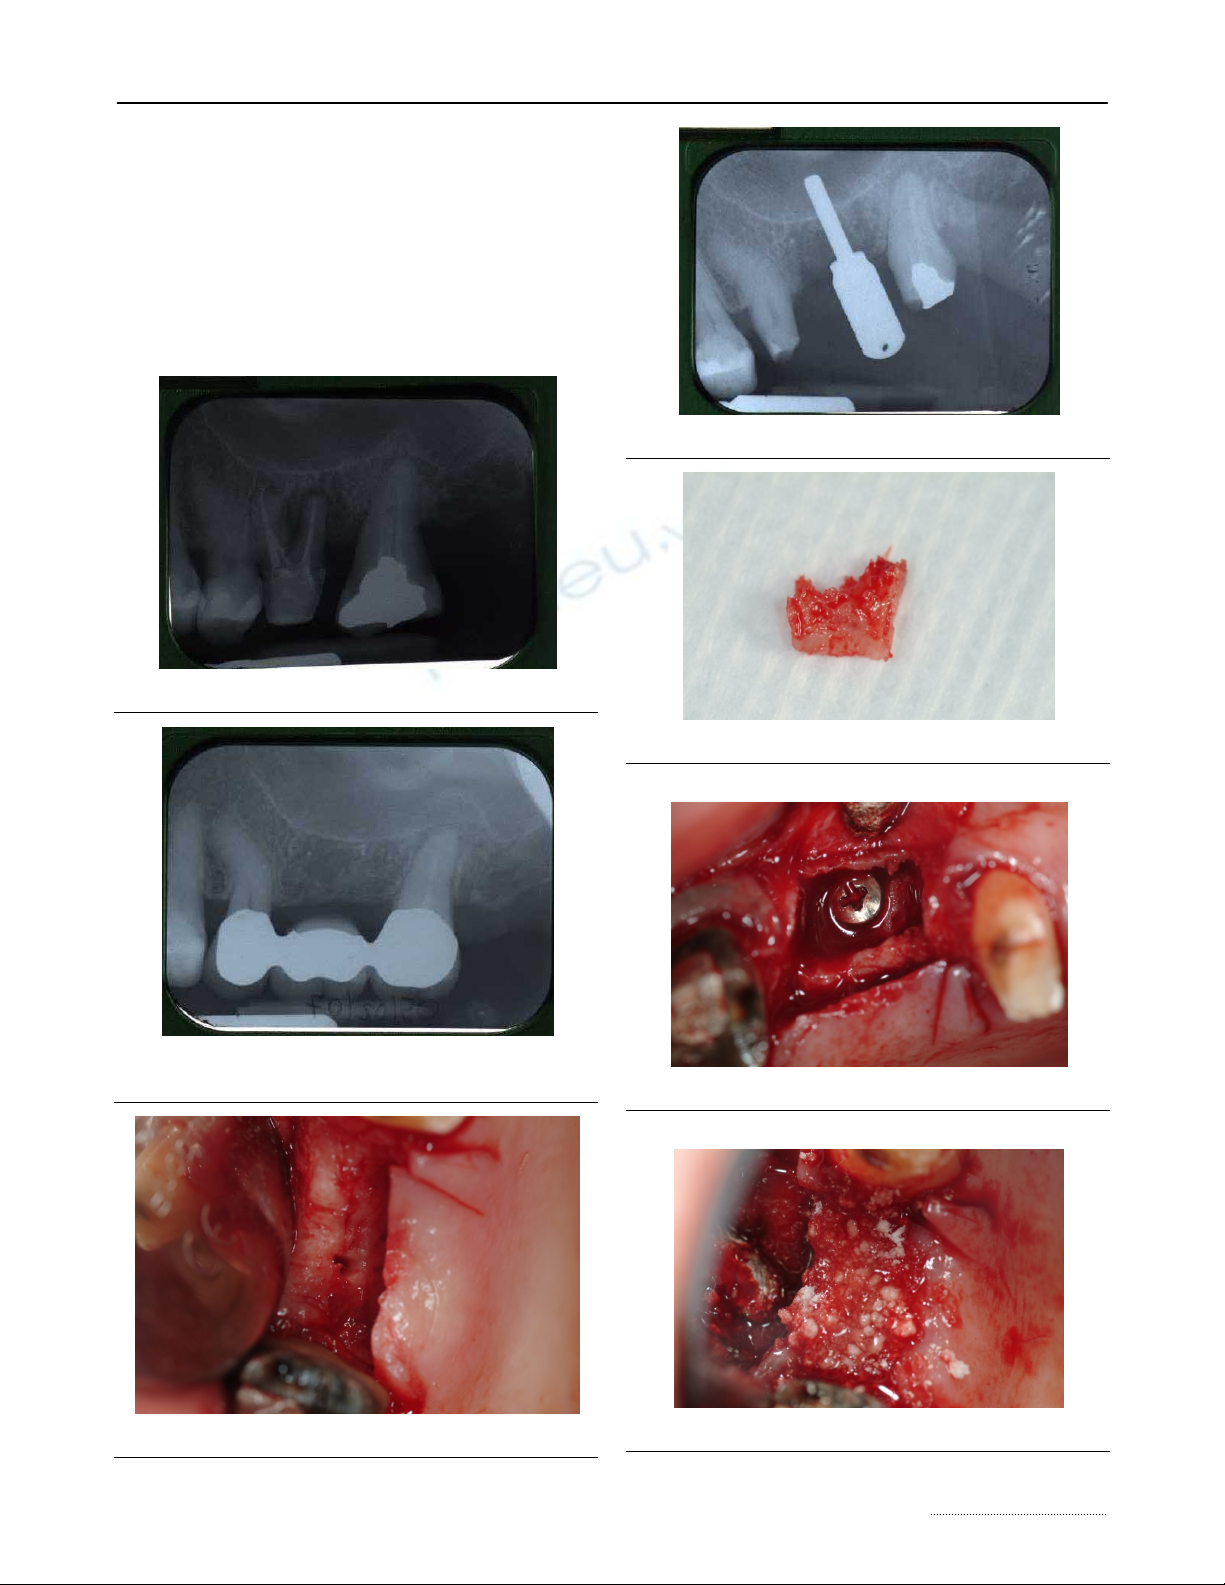

The radiographic (Fig.2) examination did not

underline any discontinuity of the sinus floor, but

showed radiographic loss of lamina dura at the infe-

rior border of the maxillary sinus over the involved

tooth and the localized swelling and thickening of the

sinus mucosa; only close the root of 2.7 a periapical

lesion was present; radiopacity of different degrees

was evident in sinus space.

An explorative surgery was planned in order to

evaluate the presence of a possible communication.

A buccal full thickness flap was harvested and

the presence of a small OAF was verified. (Fig.3).

After the evaluation of OAF dimensions (Fig. 4),

the surgical procedure was conducted by performing

an incision on the bone tissue surrounding the lesion

with bone drills and by harvesting a squared wedge

bone on the alveolar ridge, in order to avoid the per-

sistence of fibrotic tissue and to permit an adequate

bleeding.

An autologous bone graft was taken by a conti-

guous cortical site using a trephine with an inner

diameter matching the size of the bony defect. (Fig. 5).

The graft was press-fit into the defect and a

screw was inserted for internal fixation to increase

stability (Fig. 6).

The remaining vertical bone defect was filled

with a xenogenous bone graft (BIOSS®) (Fig 7), asso-

ciated to an expanded polytetrafluoroethylene tita-

nium-reinforced membrane (Gore-Tex ®).

Figure 1. Rx after endodontic therapy of tooth 26.

Figure 2. Rx after 26 extraction and following rehabilita-

tion with fixed partial prosthesis.

Figure 3. Flap elevation.

Figure 4. Demonstration of OAF existence by pin.

Figure 5. Autologous bone.

Figure 6. Graft stabilized with screw.

Figure 7. Defect filling with xenologous bone.